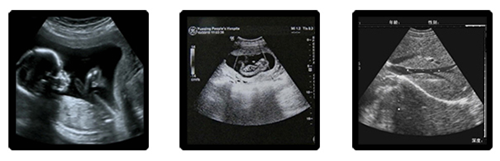

安琪兒婦產(chǎn)醫(yī)院斥巨資引進(jìn)美國(guó)Voluson E8 TruScan四維彩超,其出色的人體工程學(xué)設(shè)計(jì),每秒鐘可實(shí)時(shí)獲得46幅容積圖像,能直觀、立體的觀察和顯示人體器官的動(dòng)態(tài)和三維結(jié)構(gòu),通過(guò)四維(全方位)立體成像,清晰并動(dòng)態(tài)記錄寶寶在子宮內(nèi)的活動(dòng)和成長(zhǎng)歷程。該技術(shù)獲得美國(guó)FDA認(rèn)證,不存在射線,光波和電磁波等方面的輻射,為您和寶寶提供健康保障,使您輕松愉悅的享受和寶寶的第一次“約會(huì)”。

(1) 胎兒頭顱-顱骨強(qiáng)回聲環(huán),腦中線,側(cè)腦室,后顱窩池

(2) 胎兒脊柱-排列,連續(xù)性

(3) 胎兒心臟-顯示并觀察四腔心切面

(4) 胎兒腹部-觀察腹壁,臍帶腹壁入口,肝,胃,雙腎,膀胱

(5) 胎兒四肢-顯示一般股骨并測(cè)量股骨長(zhǎng)度,顯示一側(cè)肱骨并測(cè)量肱骨長(zhǎng)度

安琪兒婦產(chǎn)醫(yī)院對(duì)產(chǎn)科超聲檢查的要求非常嚴(yán)謹(jǐn),按照相關(guān)部門的有關(guān)規(guī)定,完善統(tǒng)一規(guī)范的檢查指征,并嚴(yán)格執(zhí)行,院方也要求醫(yī)生嚴(yán)格執(zhí)行產(chǎn)科超聲操作規(guī)范,盡量降低胎兒畸形的漏診情況出現(xiàn)。